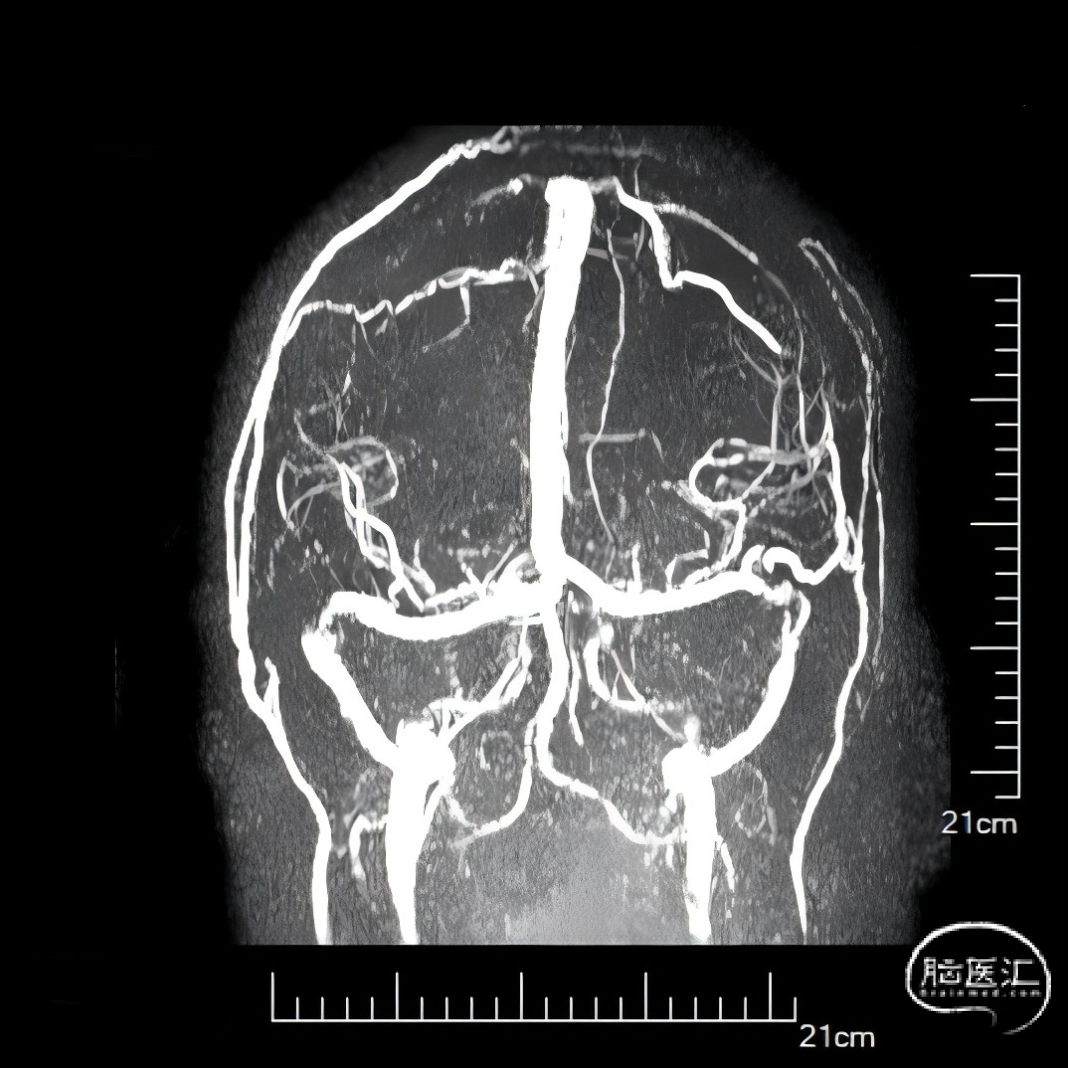

经中间管手推造影,确认血栓位置。

球扩后造影,上矢状窦接触溶栓尿激酶20万U。

球囊扩张和接触溶栓后,再次经中间管反复抽吸后复查造影。

再次给予尿激酶10万U后复查造影。

再次给予球囊扩张,球扩后复查造影。

第二次术后次日复查头CT,置管溶栓3天后(4月6日)拔除微导管及静脉鞘,复查头颅MRV。